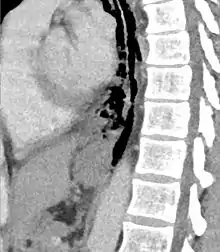

The diagnosis of Boerhaave's syndrome is suggested on the plain chest radiography and confirmed by chest CT scan. The initial plain chest radiograph is almost always abnormal in patients with Boerhaave's syndrome and usually reveals mediastinal or free peritoneal air as the initial radiologic manifestation. With cervical esophageal perforations, plain films of the neck show air in the soft tissues of the prevertebral space.

Hours to days later, pleural effusion(s) with or without pneumothorax, widened mediastinum, and subcutaneous emphysema is typically seen. CT scan may show esophageal wall edema and thickening, extraesophageal air, periesophageal fluid with or without gas bubbles, mediastinal widening, and air and fluid in the pleural spaces, retroperitoneum or lesser sac.